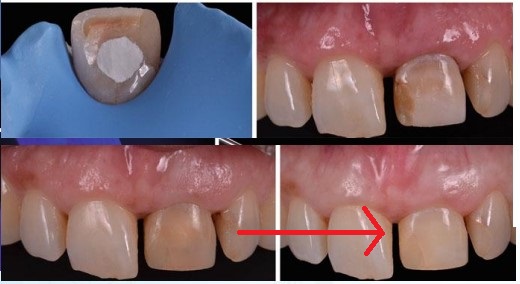

실활치미백

위의 그림은 변색된 치아의 치아미백치료입니다.

(실활치미백)